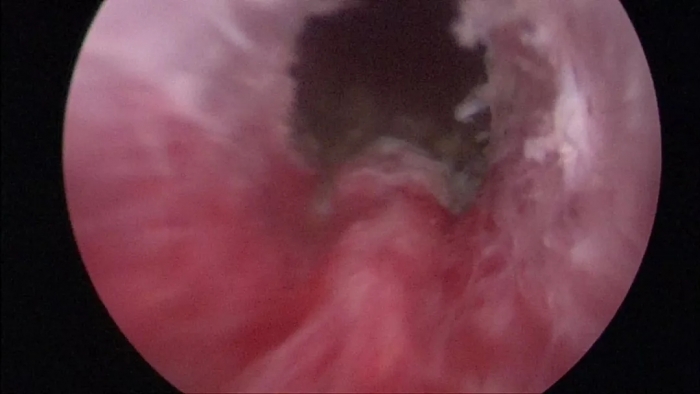

(“前列腺等离子微创电切术”示意图)

什么是经尿道前列腺等离子微创电切术?

经尿道“前列腺等离子微创电切术”是指经尿道插入双极等离子微创电切镜,在直视下切除前列腺增生突入尿道的部分,这是目前国际治疗前列腺增生的“金标准”。

经尿道“前列腺等离子微创电切术”(PKRP)是一种“安全性高、并发症少、疗效确切”的手术方法。